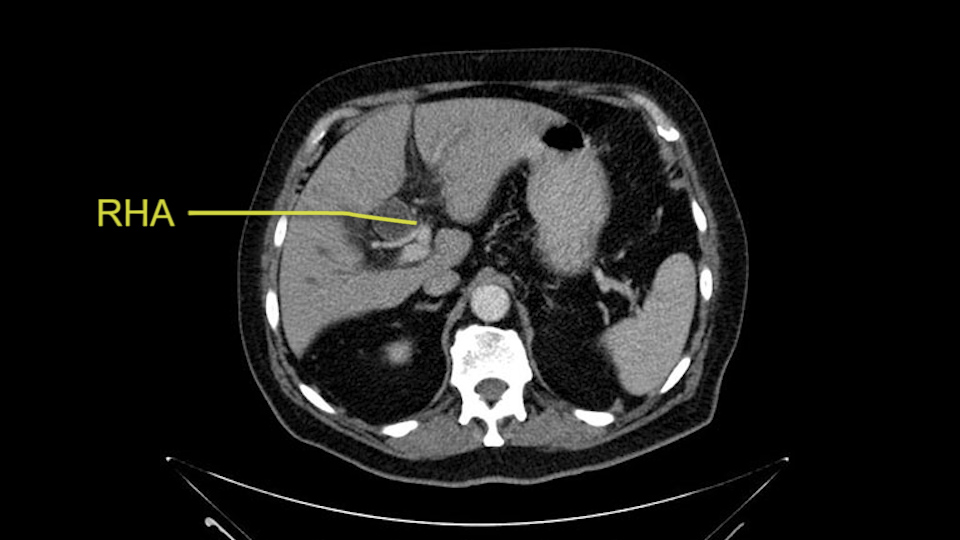

Then you look for anomalies. The one you worry about the most doing a Whipple is a replaced or aberrant right hepatic artery coming off the SMA at its origin. So again, find the SMA. You can find it because the renal vein goes through it. Follow it up, up-up-up. Nothing coming off of there that I can see here. Nothing coming off of it, nothing coming off of it and just to confirm it, look at the celiac trfurcation. There’s the celiac, there’s the bifurcation, there's the splenic artery, hepatic artery. Make sure there’s a right, which there is here. The right usually goes under the bile duct: important when you’re going around the bile duct to do a Whipple. A replaced right goes under the portal vein and the bile duct way over here on the right. That’s about it.

The other slowing down moment would be the gastroduodenal artery. Confirming that the gastroduodenal artery is not a dominant artery supplying blood to the liver. Liver failure is something which we don’t want due to altered blood supply to the liver or hampered arterial blood supply to the liver. So I would dissect out the hepatic artery, the left and right branches very clearly. Put a bulldog clamp on the gastroduodenal artery, make sure that the perfusion of the liver is excellent on the right and left side, and then divide the gastroduodenal artery. I would avoid using crushing instruments or crushing clamps on the gastroduodenal artery because they have a tendency to shatter in patients who are old with friable vessels so you have to be careful and tackle it with the help of a 5-0 or a 6-0 prolene sutures. In younger patients, I would just apply clips and move on when it comes to dividing the gastroduodenal artery.

The second point about the vascular anatomy-, is to again look for right hepatic arteries in the hilum, coming from the superior mesenteric artery by palpating-through the Winslow Hiatus. Usually we will check for a pulse in the posterior aspect of the hepatic hilum, where a right hepatic artery should not usually be found. In this case, the precaution is to avoid an accidental ligation of the right hepatic artery that might jeopardize perfusion of the right lobe, or if there is a completely replaced hepatic artery that can put the liver circulation at risk.

I am a believer in pylorus preservation. And in this case I see no reason why that wouldn't be possible. Mobilize the duodenum, divide the gastroepiploic vessels and divide the duodenum. I try to divide it with a linear stapler about four centimeters from the pylorus to have adequate length for my GI anastomosis. This facilitates exposure of the head neck of the pancreas. I find the gastroduodenal artery. This patient has normal arterial anatomy. Always on every preoperative CT scan I look to see if there is a replaced right hepatic. In this case I did not see one. Regardless of how confident I am I always look carefully for variant anatomy. I always do a clamp test on the GDA before ligation. I doubly ligate the GDA with not just a tie but a suture ligature because of the risk of GDA blowout in patients with a leak.